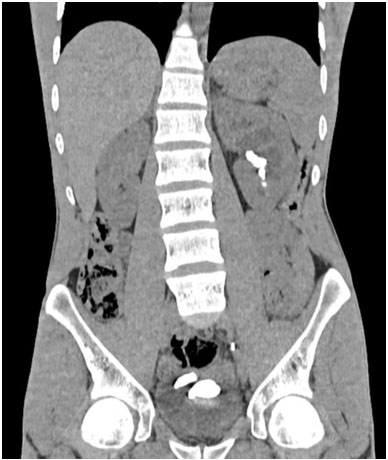

A computed tomography scan performed on February 8, 2023 revealed a left renal stone measuring 20×8 mm in the renal pelvis, with calcific density causing significant upstream dilation and stasis stones involving various calyceal groups. The double J stent was in place, with the upper loop positioned at the level of the iliac ureter, and signs of encrustation were observed at the lower loop (Figure 1 and Figure 2).

Figure 2: An abdominal CT scan without contrast injection showing the presence of calculi in the middle and lower calyces, with encrustation in bladder.